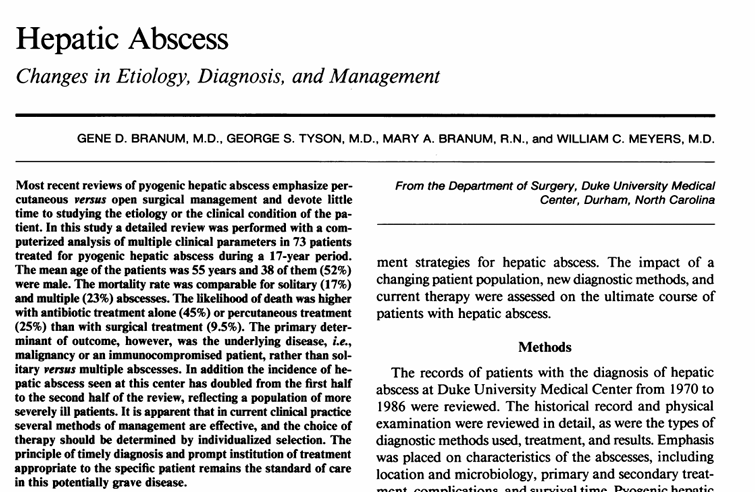

이 논문에서 주장하는 내용을 가져왔습니다.

이 표 보시면 Biliary disease가 제일 많은 기저질환을 차지하며, 장염, Hematologenous disease, pancreatitis 등도 기저질환 중 하나임을 설명하고 있습니다.

- pancreatitis (→ sphincter of Oddi dysfunction)

- cholangitis / biliary disease

- enteritis / dysbiosis

- portal bacteremia

즉 이 4가지 기전이 간 농양 유발 핵심 원인으로 설명하고 있습니다.